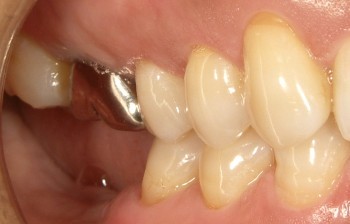

インプラントの術前・術後 Nさん